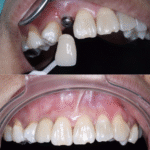

ฟันโยกทั้งปาก ฟันเสียหลายซี่มาก ต้องทำรากเทียม

ทั้งหมดเกือบ 10 ซี่ หลังทำเสร็จหนุ่มขึ้นมาก อยากกิน

อะไรก็กินได้ ตอนทำเจ็บนิดเดียว — คุณทนงศักดิ์